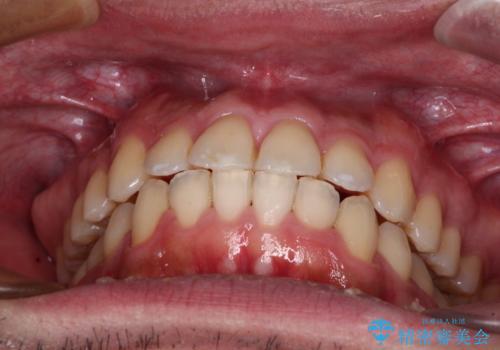

- 前歯のデコボコを治したいとのことで来院された患者様です。

できる限り楽して、短期間で治したいとのことで、ワイヤー装置にて矯正治療を行うこととしました。